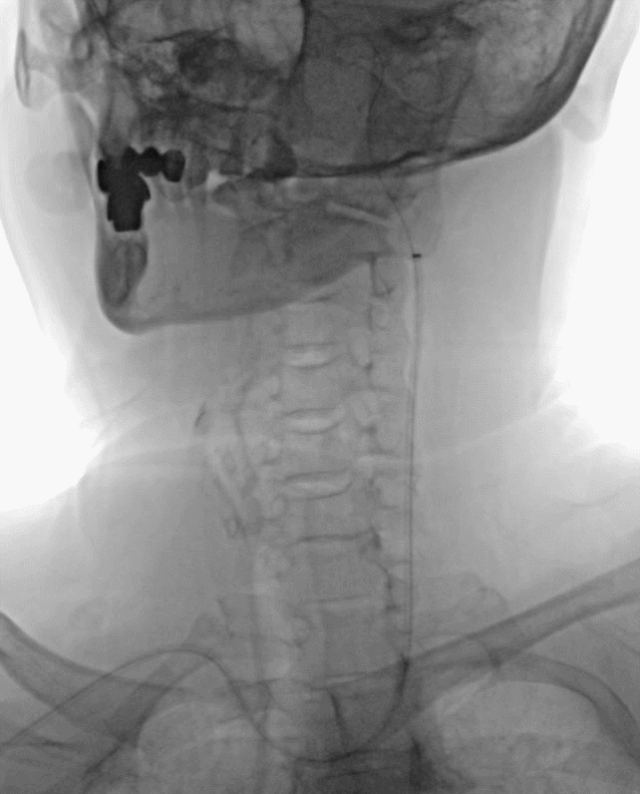

5F 125cm Sim2造影导管携5.5F Introsky X导管鞘成袢后超选左侧ICA。

泥鳅导丝、SIM2造影导管、5.5F Introsky X导管鞘同轴下继续跟进,尽可能高到位,随后引入V-18导丝。